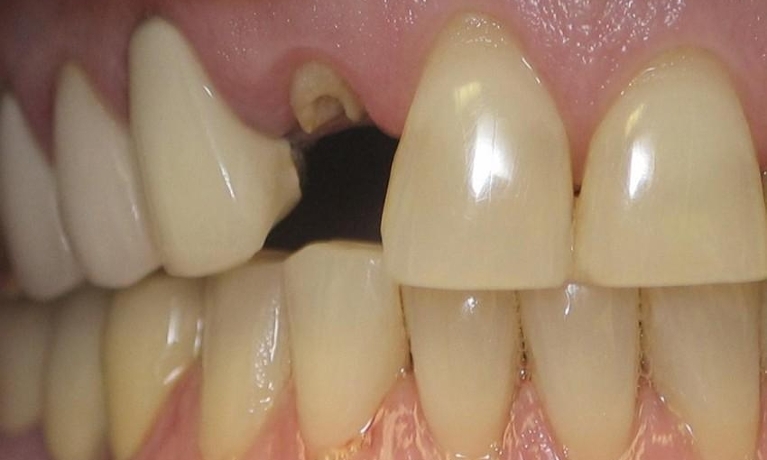

Smile Gallery

Are you considering dentistry at Michael J Nelson DDS? If so, we’d like to invite you to browse our Smile Gallery. Our dental team can improve your oral health and help you attain the attractive smile you’ve always wanted.